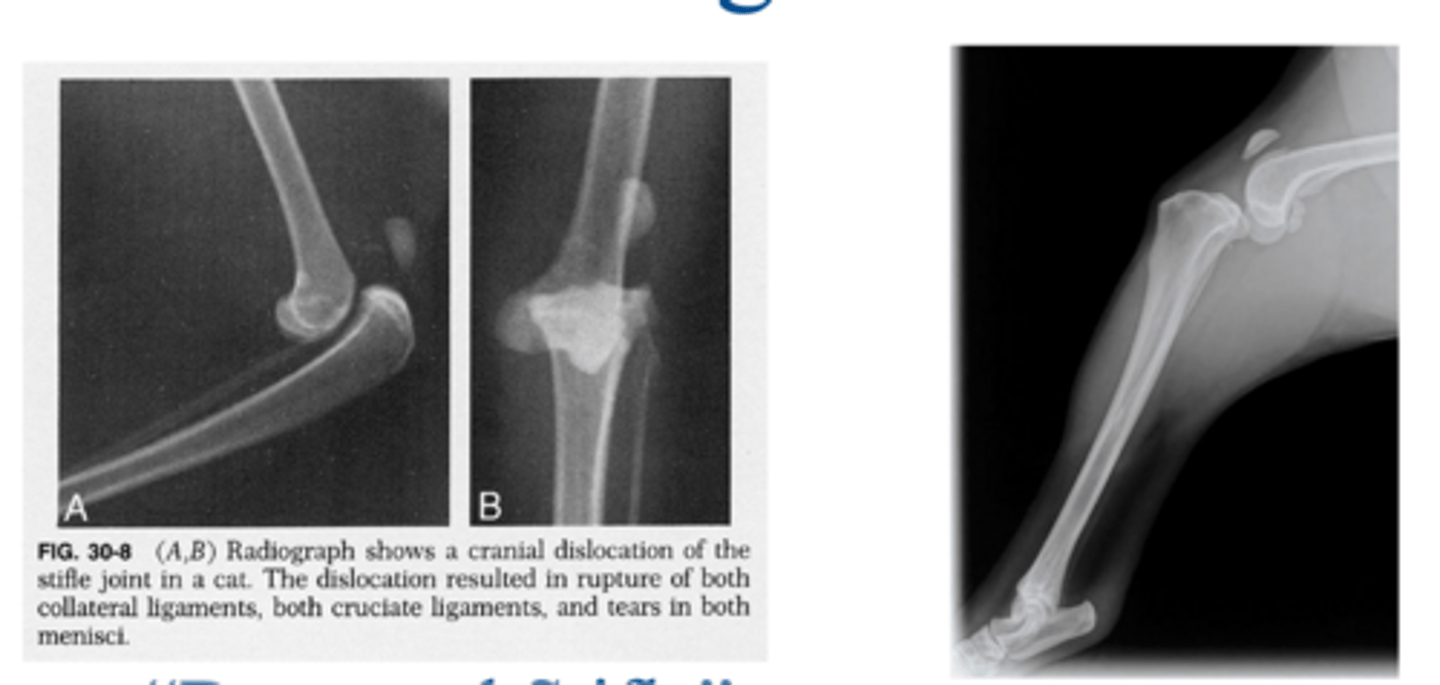

deranged stifle...multiple lig. injuries often associated w/ meniscal injury and stifle luxation

what condition is shown here